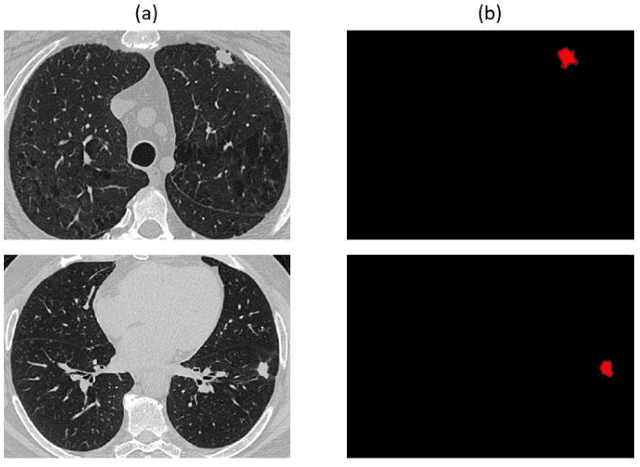

Non-small cell lung cancer (NSCLC) is a serious disease and has a high recurrence rate after the surgery. Recently, many machine learning methods have been proposed for recurrence prediction. The methods using gene data have high prediction accuracy but require high cost. Although the radiomics signatures using only CT image are not expensive, its accuracy is relatively low. In this paper, we propose a genotype-guided radiomics method (GGR) for obtaining high prediction accuracy with low cost. We used a public radiogenomics dataset of NSCLC, which includes CT images and gene data. The proposed method is a two-step method, which consists of two models. The first model is a gene estimation model, which is used to estimate the gene expression from radiomics features and deep features extracted from computer tomography (CT) image. The second model is used to predict the recurrence using the estimated gene expression data. The proposed GGR method designed based on hybrid features which is combination of handcrafted-based and deep learning-based. The experiments demonstrated that the prediction accuracy can be improved significantly from 78.61% (existing radiomics method) and 79.14% (deep learning method) to 83.28% by the proposed GGR.